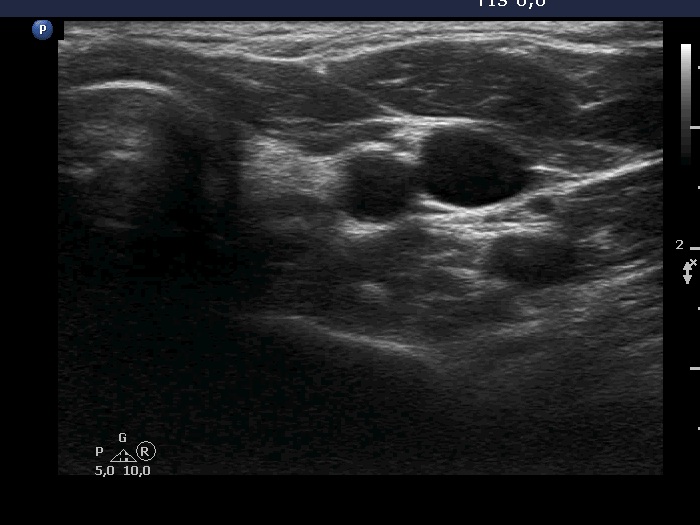

Ultrasonography. There was a hypoechoic lesion which had microcalcifications in the left thyroid bed. The dimensions were 5x5x7 mm.

Cytology resulted in papillary cancer.